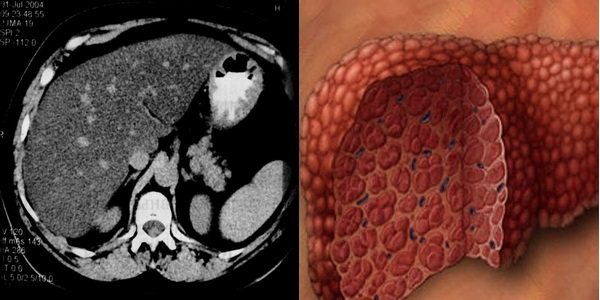

На фото печень при жировом гепатозе 3 степени в разрезежировом гепатозе 3 степени в разрезе на макропрепарате и при КТ исследовании пациента: